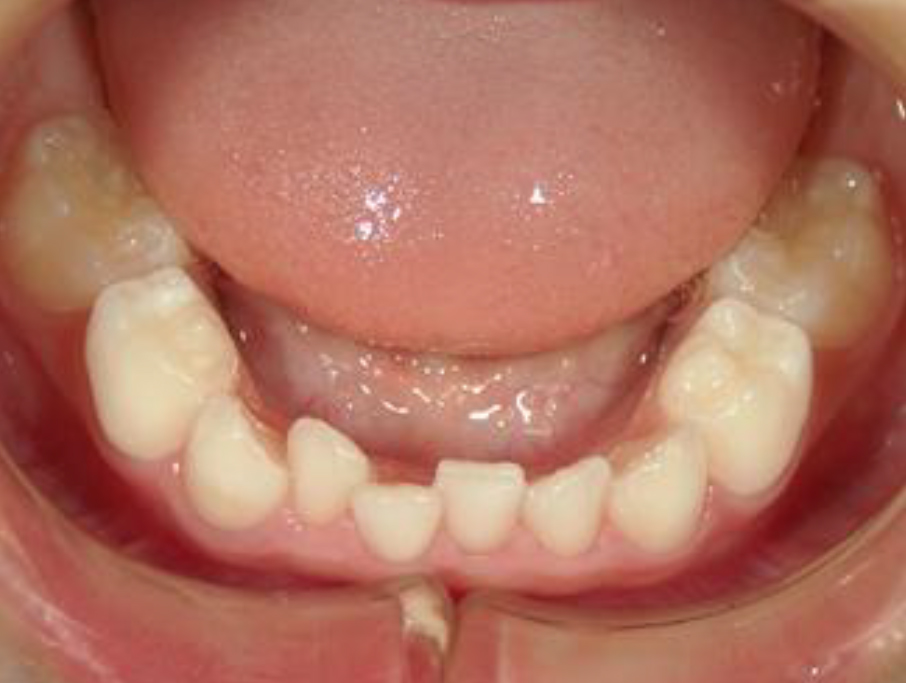

上記の基準について口腔内写真を提示すると下記のようになる。

• ⑤ 叢 生